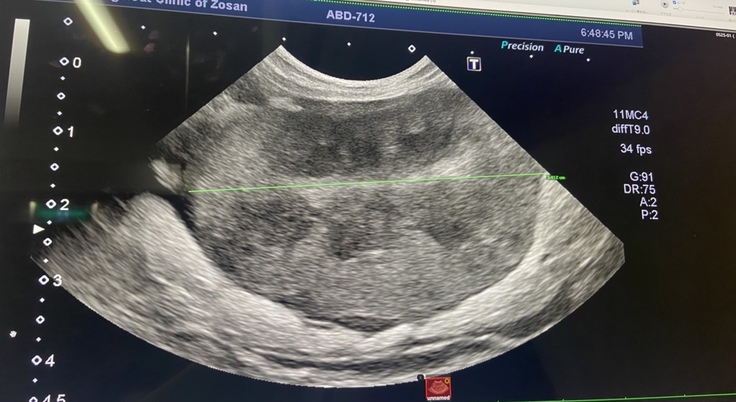

↓エコー検査の腎臓の画像↓

健康な猫ちゃんの腎臓の大きさは3cm程度ですが、

ゴマの場合、炎症を起こしなんと5.412cmまで腫れ上がっていました。